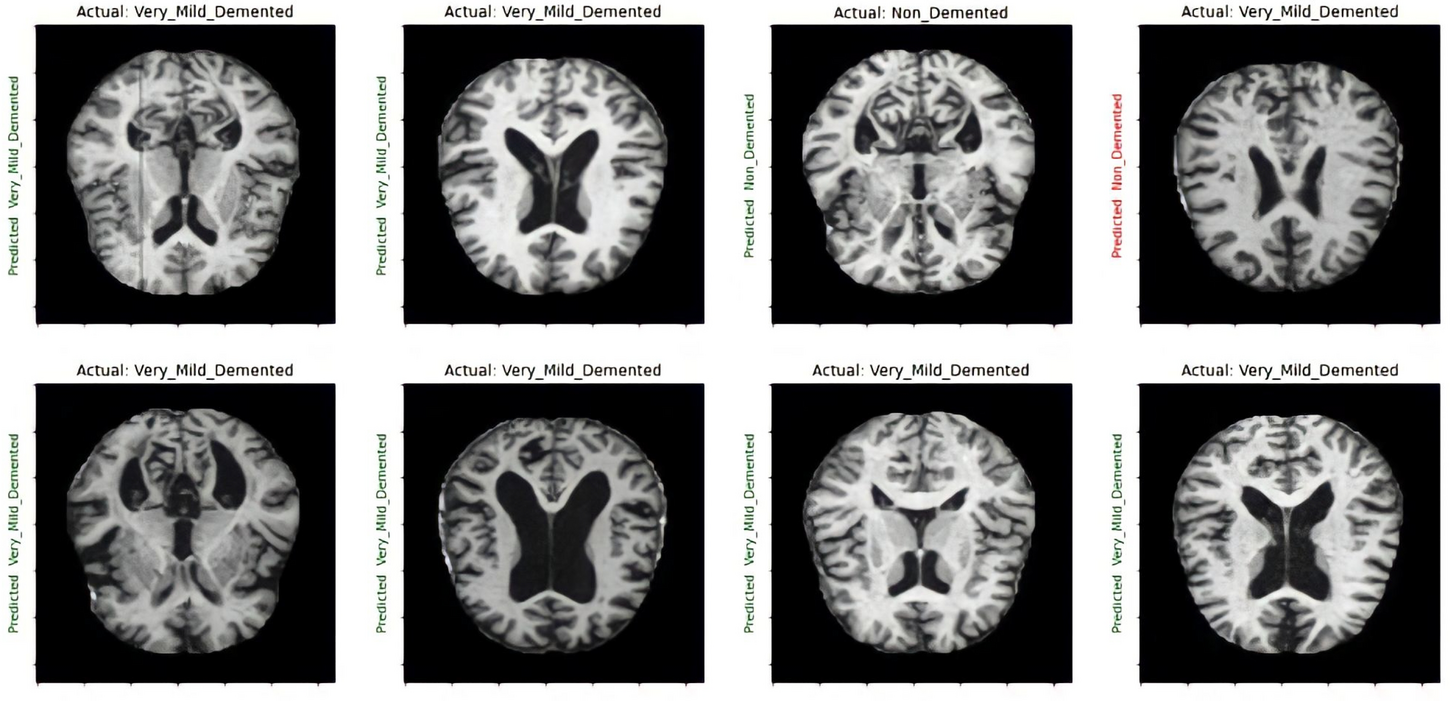

Prediction result for VGG-16 model.